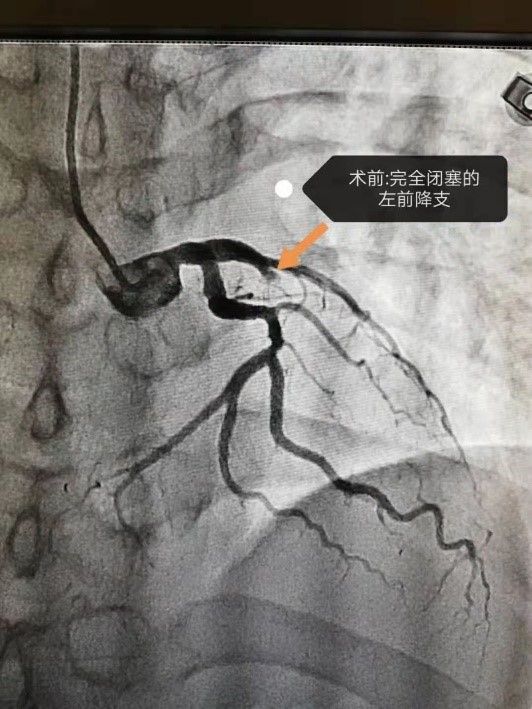

抢救从确诊那一刻就开始了 。 急诊胸痛介入团队立即进行急诊PCI手术 , 迅速将患者转入导管室 , 给予球囊扩张及支架置入术 。 “手术中患者出现无复流现象 , 也就是说心脏无法供血 , 患者已经休克了 。 ”心血管内科主任时学昆介绍 。

经过积极抢救 , 手术顺利开通闭塞血管 , 患者转危为安 , 即将康复出院 。 “万幸妇儿医院开了城阳院区 , 从家五六分钟就过来了 , 再迟一些我不敢想象后果 。 ”回忆起大年初三那天 , 王先生仍感到后怕 。